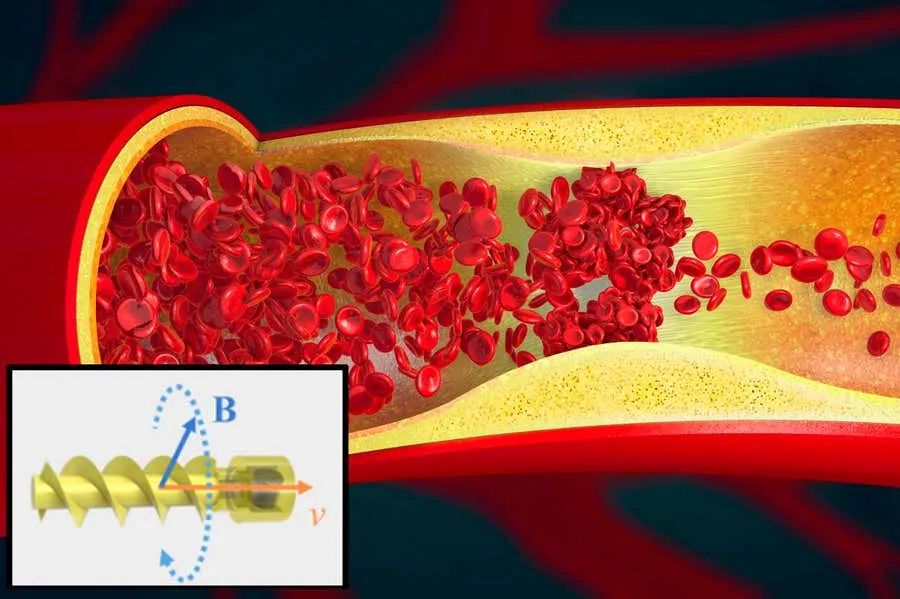

随着科技的发展,微型机器人越来越受到大家的关注。如果有一只机器鱼能依靠磁控在血管中逆流而上,会是一种什么样的情景?

材料科学和微纳制造技术的发展,使毫米或亚毫米尺寸的微型软机器人可以被制造和远程驱动。同时,小型机器人也具有以非入侵方式进入人体难以到达区域的独特本领。不过到目前为止,微型机器人在人体多样化和动态的环境(如血液流动)中准确移动仍然具有挑战性。

为了解决这项难题,近日,香港中文大学、深圳人工智能与机器人710公海寰宇和多伦多大学的研发团队设计了一款能够在流体环境中进行超快游泳的微型游泳机器人。这是一种磁驱软体鱼,研究人员还展示了其能够在血管中运动的潜力。

据悉,这款磁驱软体鱼在水中的最大速度可达30 cm/s(60 BL/s),在仿血管状环境中可以达到17 cm/s的游泳速度。当流速为10 cm/s时,磁驱软体鱼也可以以5 cm/s进行逆游。同时,研究人员还展示了一种超声波导航成像功能。

该项研究证实了磁驱软体鱼可以作为药物的载体,与其他成像方法(如数字减影血管造影)和电磁设备相结合,并被快速导航到人体的目标区域,在通过血管系统进行靶向药物递送、单个细胞转运和血管疏通等方面凸显了巨大的应用潜力。